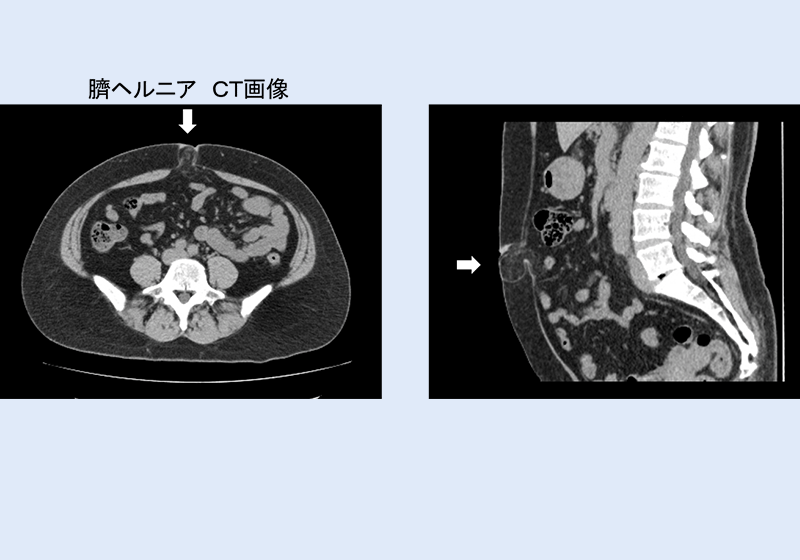

臍ヘルニアの検査

問診と診察、超音波検査(エコー検査)で容易に診断できますが、手術を行う場合はCT検査が必要になる事があります。